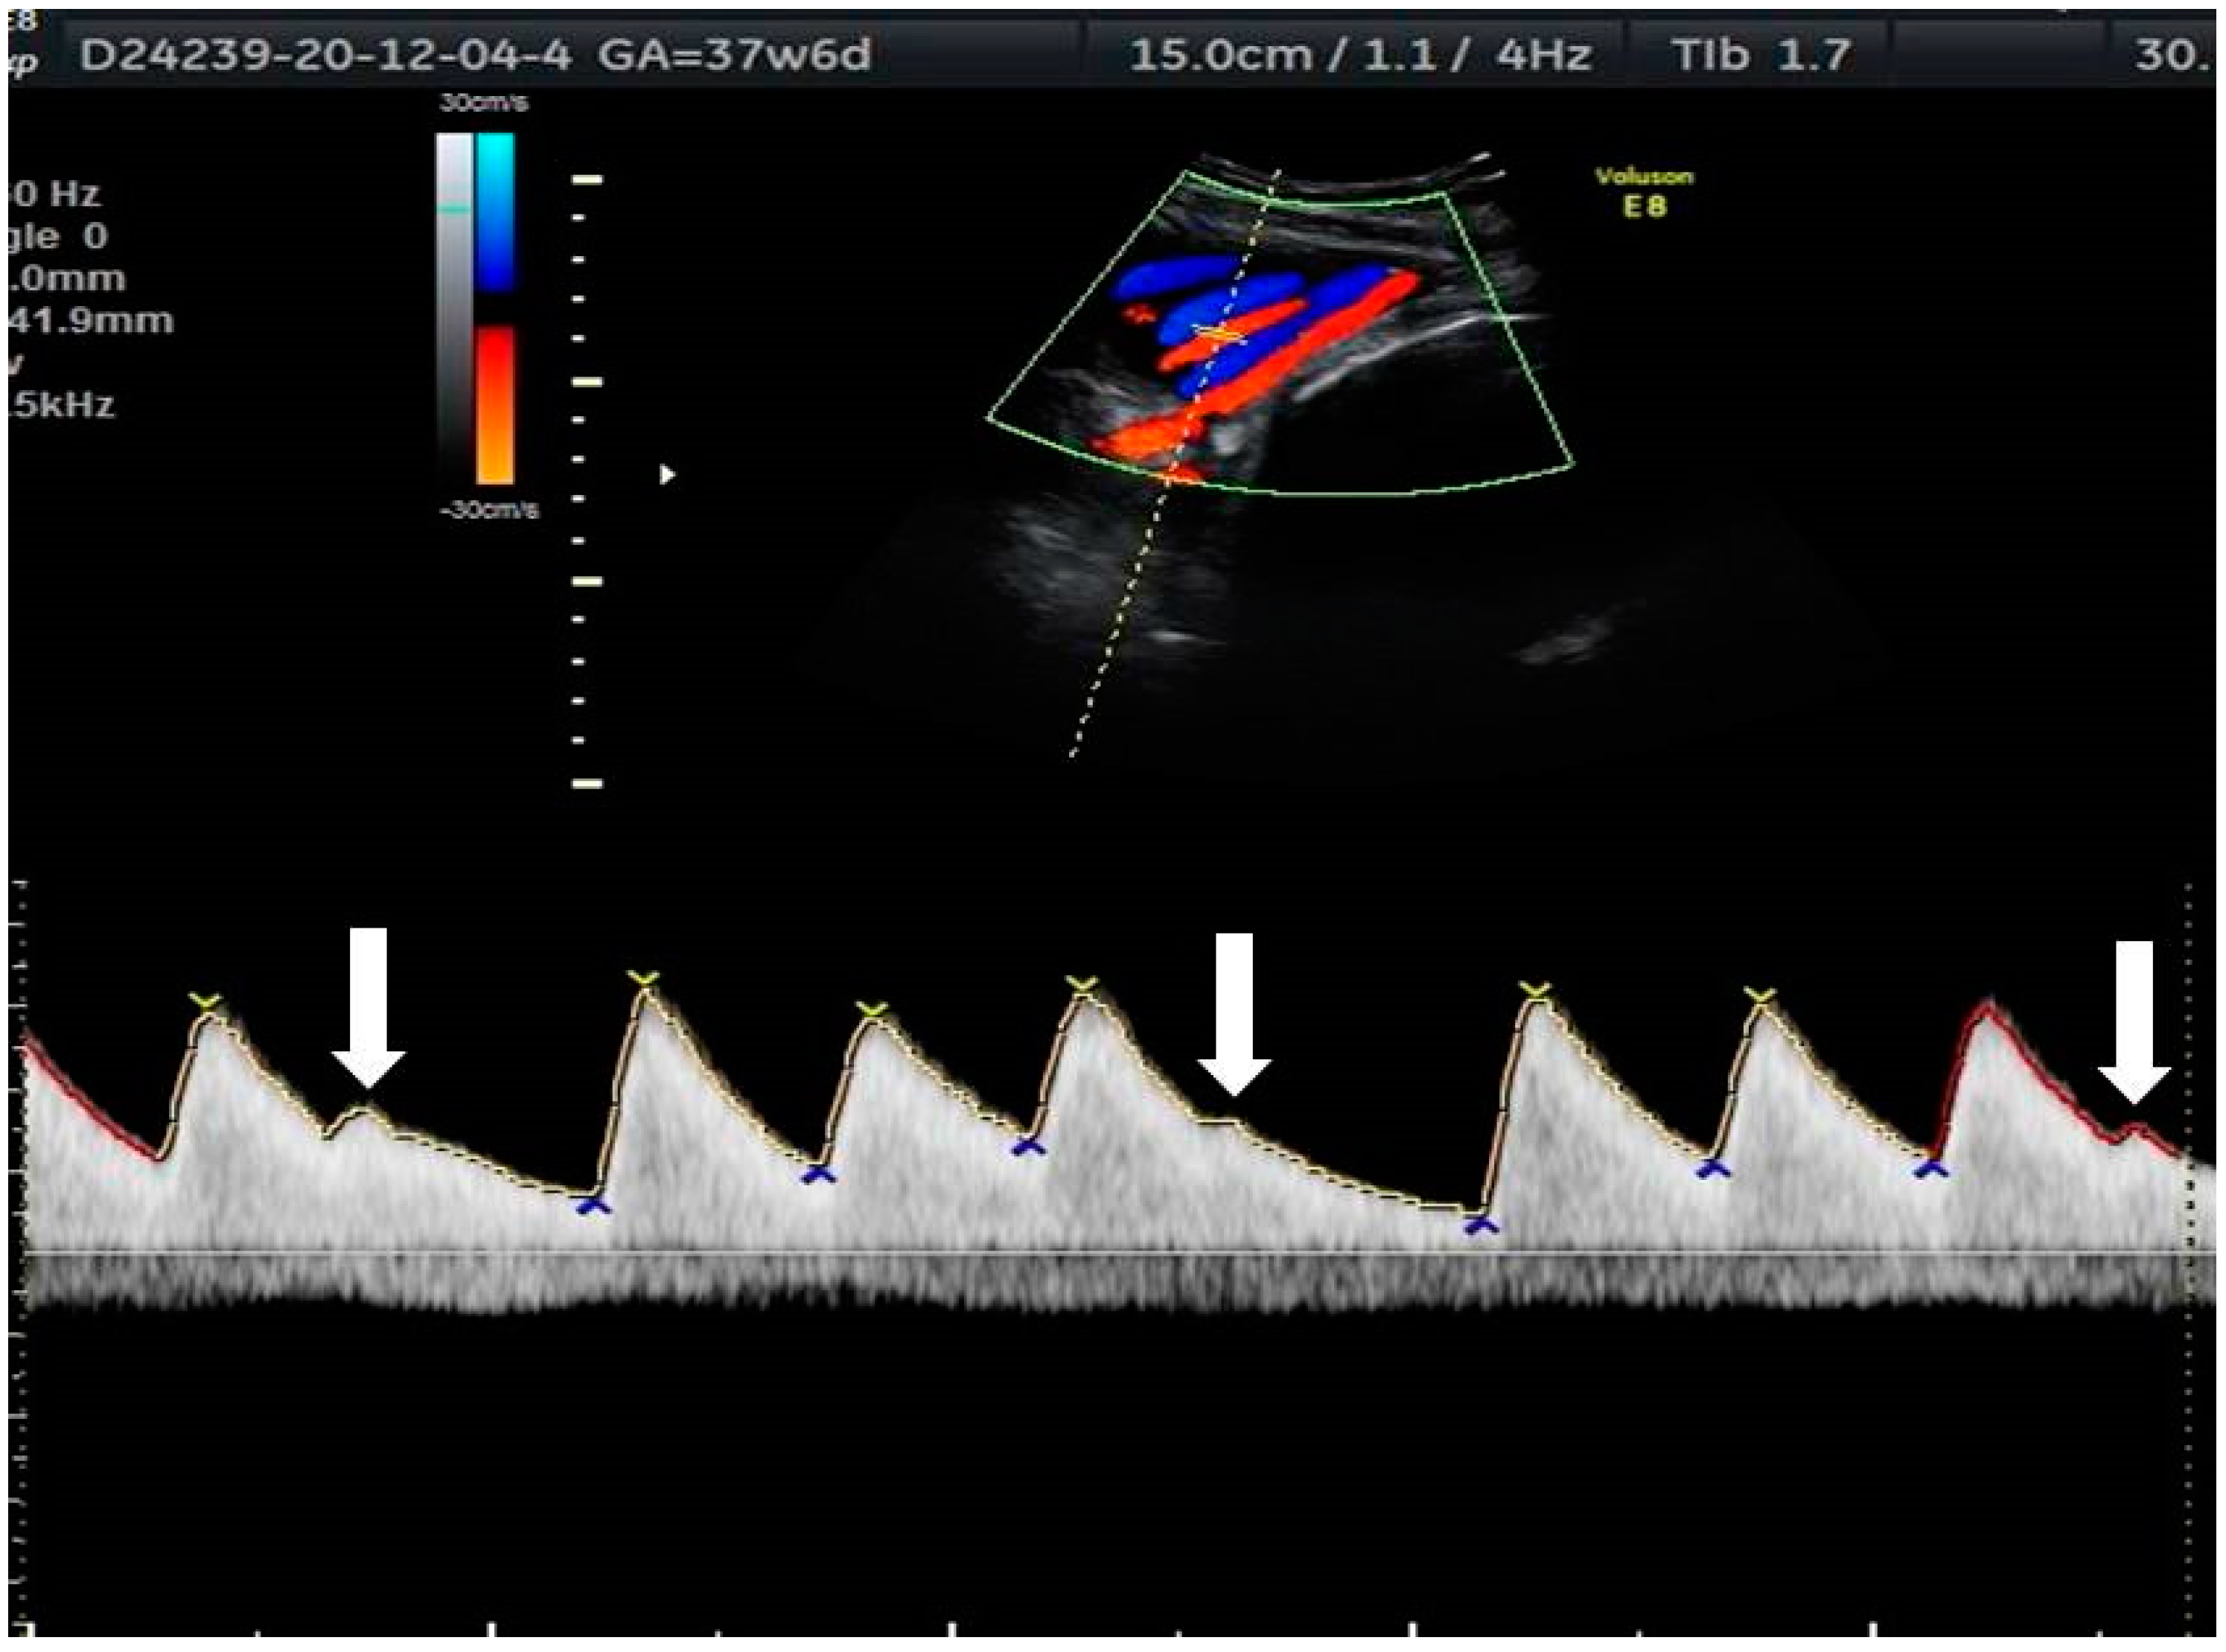

2. The Use of Ultrasound to Assess Fetal Heart Rhythm